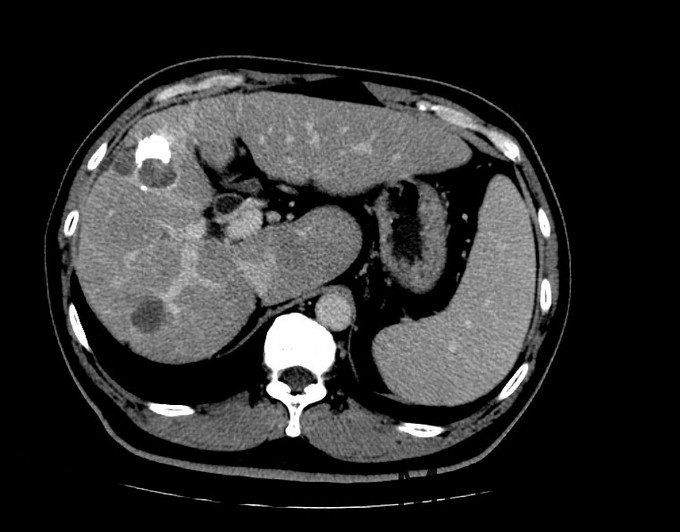

正常肝脏和肝癌ct图片,正常人肝的ct高清图片

术前ct片,左肝肿瘤考虑原发性肝癌.

肝癌CT片子图

肝癌ct

肝癌ct影像图

肝癌ct片图片图解

肝癌增强CT图片

肝癌ct图片怎么看

肝癌ct图片